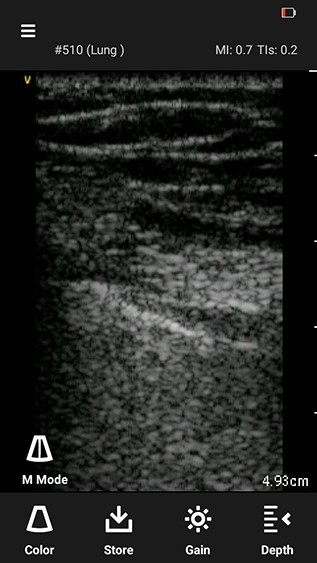

NOTE: Lung M-mode feature is enabled only for linear transducer with lung preset and sector transducer with cardiac preset.1. Press the M-mode icon. A centered vertical M-mode cursor line appears.

M-mode cursor